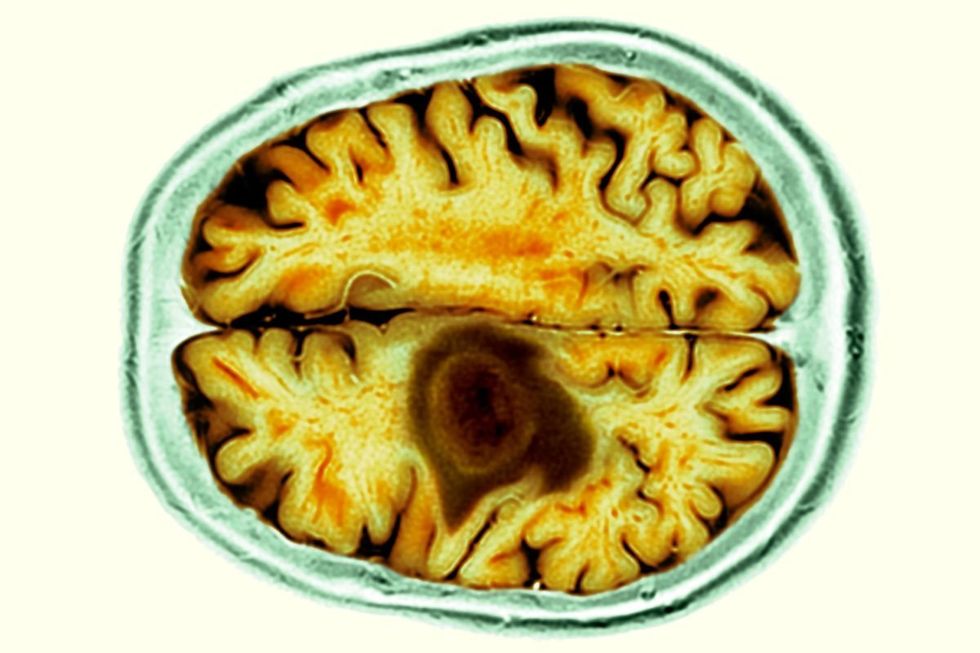

A month later, pathology results confirmed she had a high-grade glioma.

Pathology results confirmed Allison had a high-grade glioma (stock image)